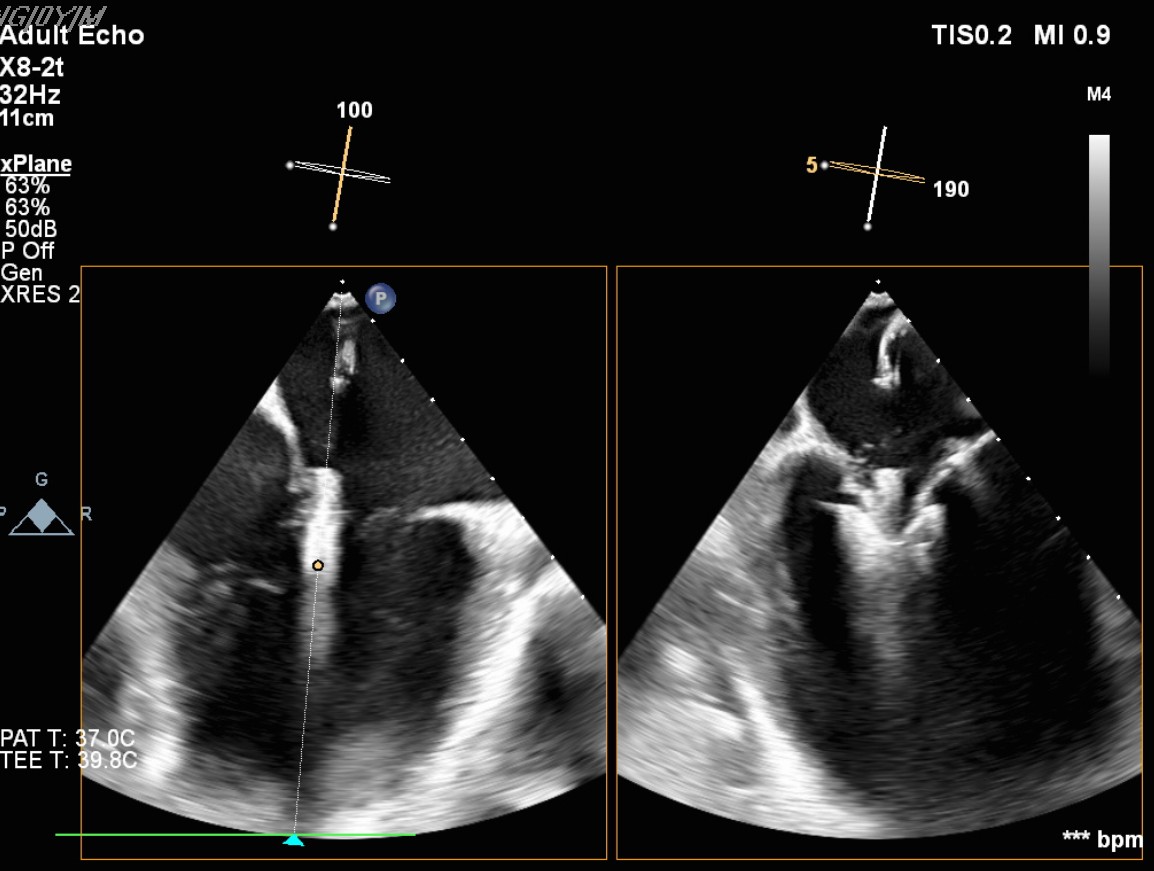

Transcatheter Edge-to-Edge Repair (Mar 27): TEE demonstrated severe mitral regurgitation with low cardiac output (~2 L/min). Two G4 XTW MitraClips were implanted successfully, improving hemodynamics.